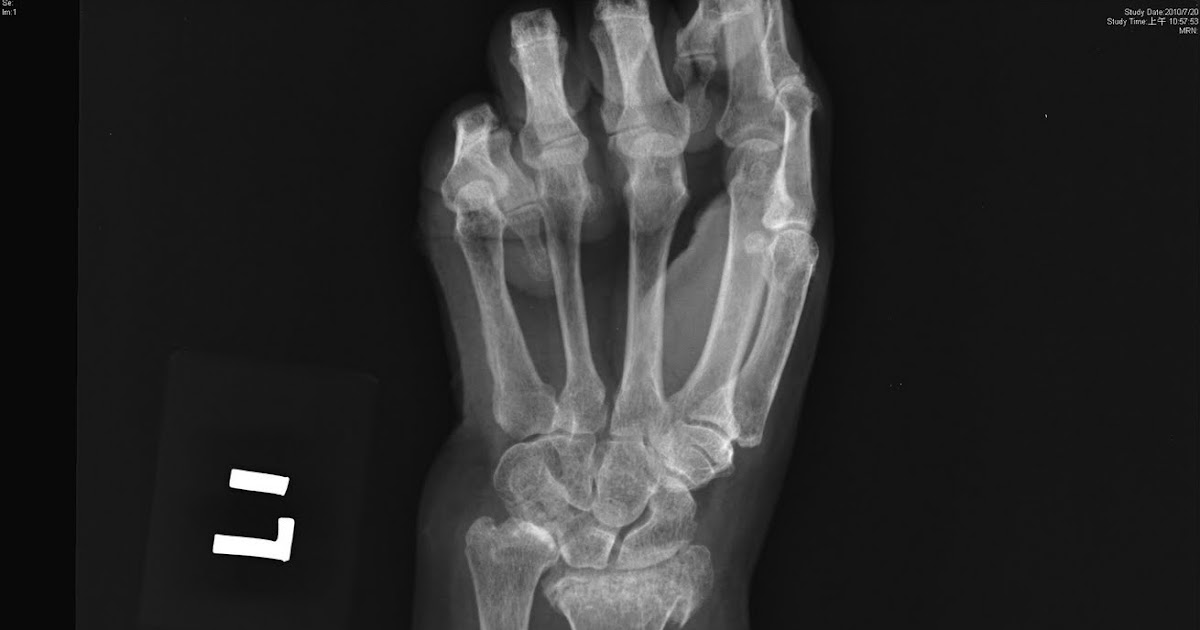

The ulna bone may also be broken. May involve articular surface frequently involving the ulnar styloid most often result from a 10: Management of distal radius fractures. These fractures have varied patterns, so a single form of treatment usually does not apply. Fracture at the metaphysis or the articulation of the distal radius. The ulna bone may also be broken. Distal radius fracture clinical practice guideline. Distal radius fractures are a predictor of subsequent fractures. Acute median and/or ulnar nerve damage (~10% of low. A distal radius fracture is a common bone fracture of the radius in the forearm. Apparent volar tilt of the surface of the distal radius, as measured on the lateral view, increases with supination and decreases with pronation of the wrist (5). The 7th character should be used when the patient. A distal radius fracture, also known as wrist fracture, is a break of the part of the radius bone which is close to the wrist. Falls are the main cause of distal radius fractures. Related online courses on physioplus. One of the most common fractures seen in the ed (1/6th of all fractures treated). Distal radius fractures occur through the distal metaphysis of the radius.